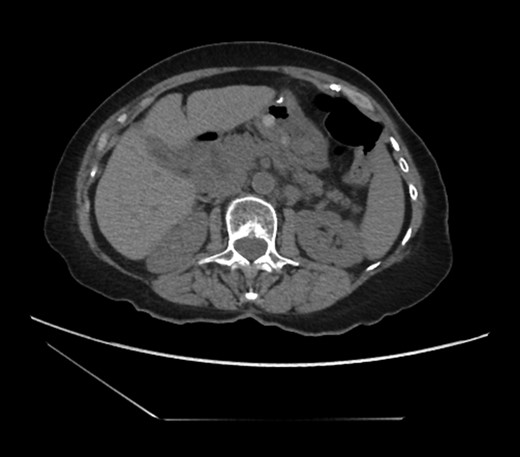

CT scan from four years prior to presentation showing evidence of foramen of Winslow hernia. Arrow head on stomach. Arrow on bowel.

Diagnosing an internal hernia is frequently accomplished using physical exam and CT imaging. Abdominal X-ray does have some nonspecific findings suggestive of internal hernia but is usually inadequate for diagnosis. Diagnosis of a foramen of Winslow hernia, however, is only accomplished in 10% of patients preoperatively [3]. As previously mentioned this diagnosis is rare and often presents with vague obstructive type symptoms. This likely contributes to the low occurrence of accurate preoperative diagnosis. However, several radiographic findings were seen in this patient that suggested a foramen of Winslow hernia preoperatively. First, there is visible swirling of the mesentery on the CT scan that is indicative of internal hernia (Fig. 1). Second, there are loops of small bowel that can be visualized between the IVC and the edge of the liver in a supra renal position along the lesser curvature of the stomach (Figs 1 and 2). When compared to a CT of the abdomen and pelvis obtained 4 years prior to presentation, there is actually evidence that this patient had a non-obstructing foramen of Winslow hernia at that time as demonstrated by bowel being visualized in the lesser sack (Fig. 5). These findings, especially small bowel along the lesser curvature of the stomach, are inconsistent with normal anatomy and strongly indicative a foramen of Winslow hernia.